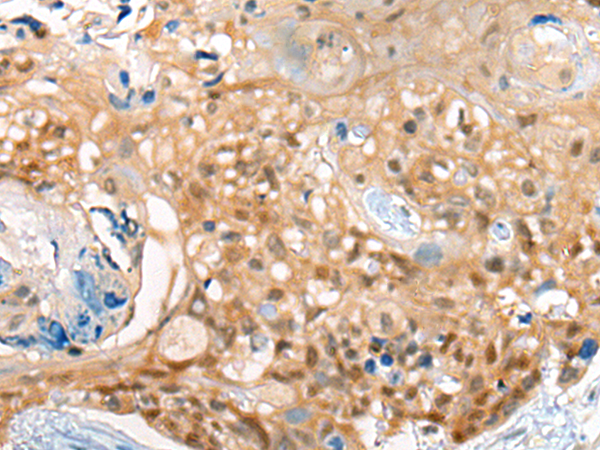

分类: 科研抗体货号: P09455别名: ST6N; SIAT1; ST6GalI应用: IHC反应种属: Human, Mouse, Rat

分类: 科研抗体货号: P09464别名: CEP2; BORG1应用: IHC反应种属: Human, Mouse, Rat